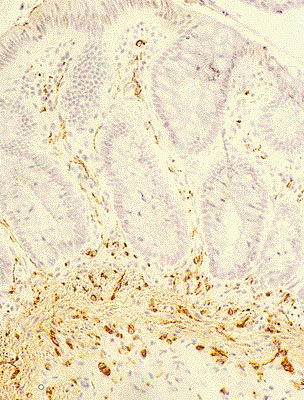

Examen histopatologic - boala Hirschsprung